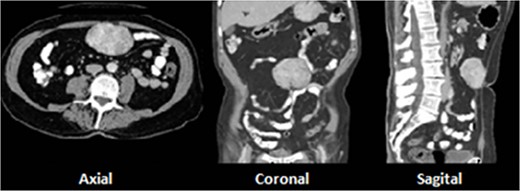

A 73-year-old male with prior history of irritable bowel syndrome presented a 2-week-long abdominal pain, located on the right lower quadrant associated with anorexia and diarrhea, without blood loss or any other symptoms. The CT-scan showed a 9-cm solid preperitoneal lesion, with enhancement following intravenous contrast administration (Fig. 1).